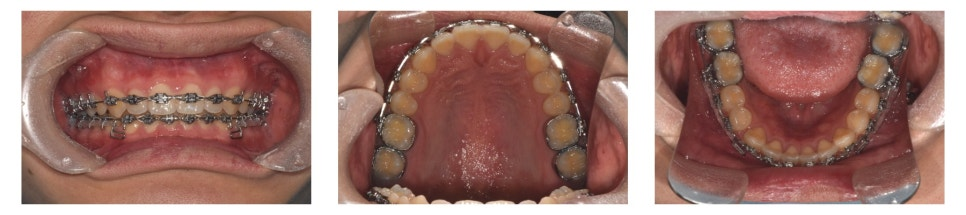

치료 시작 약 1년 4개월 후 치료를 완료하였습니다.

치료 전에는 눈에 띄게 벌어져 있던 하악 전치부의 공간(spacing)이 정상적으로 배열되었고, deep bite도 개선되어 기능적으로 안정된 교합을 얻을 수 있었습니다.

환자 또한 치료 결과에 매우 만족하였습니다.